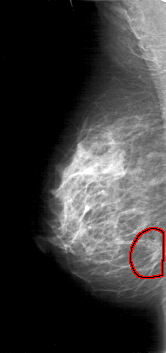

D_4030_1.RIGHT_MLO

RIGHT_MLO LINES 5281 PIXELS_PER_LINE 2476 BITS_PER_PIXEL 12 RESOLUTION 43.5 OVERLAY

FILE: D_4030_1.RIGHT_MLO.OVERLAY

TOTAL_ABNORMALITIES 1

ABNORMALITY 1

LESION_TYPE MASS SHAPE IRREGULAR MARGINS SPICULATED

ASSESSMENT 5

SUBTLETY 5

PATHOLOGY BENIGN

TOTAL_OUTLINES 1

BOUNDARY